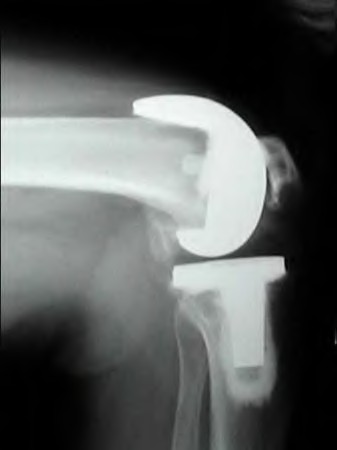

A 60-year-old male tennis player undergoes a unicompartmental knee arthroplasty (UKA) shown in Figures A and B. Which of the following statements regarding this procedure is true?

1) Compared to total knee arthroplasty (TKA), UKA more closely approximates native knee kinematics

2) Patients undergoing a UKA and TKA have equivalent blood loss and pain

medication requirements

3) Compared to their TKA counterparts, UKA patients have a slower return to function

4) There is no difference in range of motion at short or long term follow-up when compared with TKA

5) Postoperative hospital stay is equivalent for UKA and TKA patients

Figures A and B depict radiographs of a unicompartmental knee arthroplasty (UKA). UKA kinematics have been shown to most closely approximate native knee kinematics.

In an in vitro cadaver study, Patil et al found that TKA significantly changed knee kinematics while the unicompartmental replacement preserved normal knee kinematics.

Fisher et al performed a retrospective study comparing the short-term outcomes of small-incision unicompartmental knee arthroplasty (UKA) with standard total knee arthroplasty (TKA) in 91 consecutive patients older than 70 years. They found: 1) Blood loss was significantly more for the TKA group, as was the need for blood transfusion. 2) Patients with unicompartmental replacements had a much quicker return of function and discontinuation of pain medication. 3) While knee scores and ROM were similar preoperatively, both were better in the unicompartmental group at each postoperative time interval. 4) Narcotic use and length of hospital stay were also significantly less for the unicompartmental group. Therefore answers 2,3,4 and 5 are false.